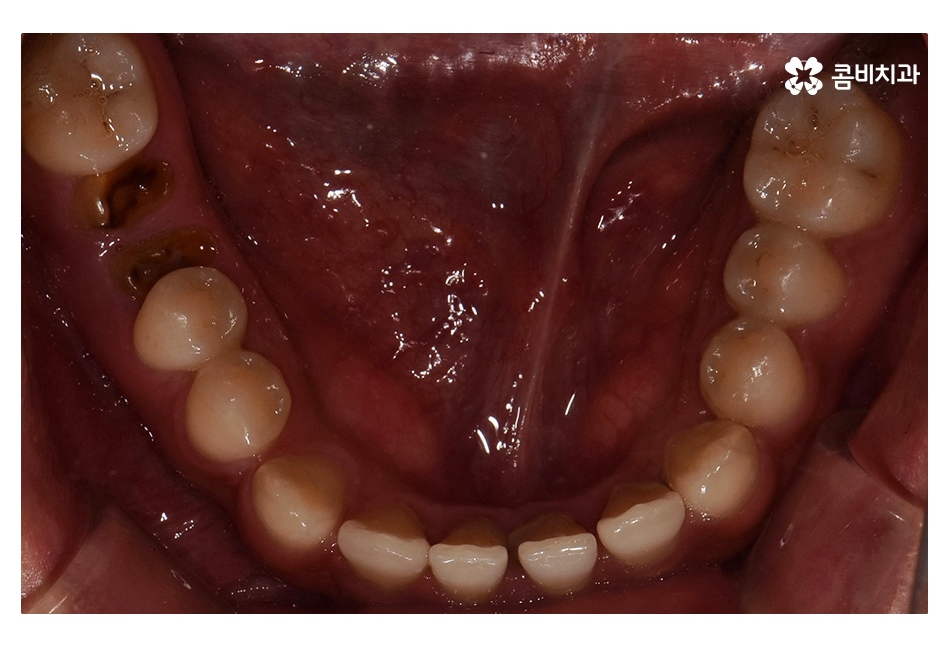

오늘 보시는 사례는 아랫니가 윗니를 덮고 있는

반대교합의 상태로 음식을 제대로 씹지 못하고

발음이 부정확하며 심미적으로도 좋지 않기 때문에

치아교정을 통해 치료가 필요한 케이스 중 하나라고 볼 수 있어요

위 환자분의 경우 충치로 인해 오른쪽 아래 제1대구치와

왼쪽아래 제2대구치가 상실된 상태였으며, 치아교정만으로는

치료가 불가능한 케이스였기 때문에 비발치 교정으로

진행하면서 외과수술이 병행된 케이스라고 할 수 있어요